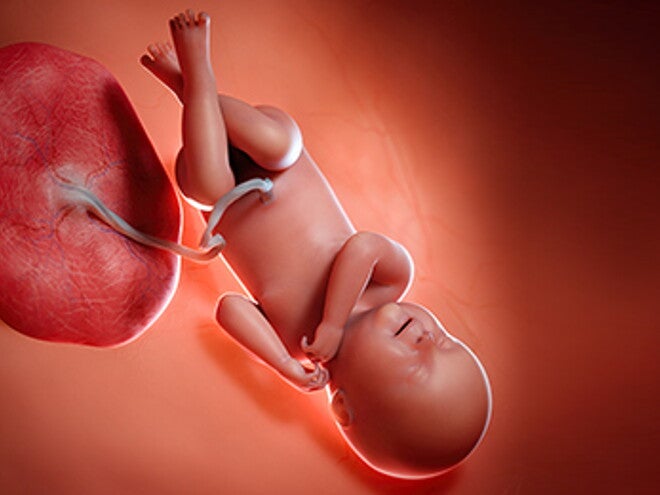

טרימסטר שלישי - כל מה שחשוב לדעת

ברגע שהגעת לשליש השלישי של ההריון, תשמחי לדעת שכבר עברת את מחצית הדרך , בין שבועות 27-40. כשמצפים לתינוק, יש הרבה תוכניות. ייתכן שתגלי שאת איטית ועייפה יותר, או דווקא מלאה באנרגיה לנקות, לסדר ולארגן. מרגש, זה כבר ממש קרוב...

השליש האחרון להריון שלך. כל המידע אודות החלק האחרון של הריונך - רגע לפני שילדך יוצא לאוויר העולם